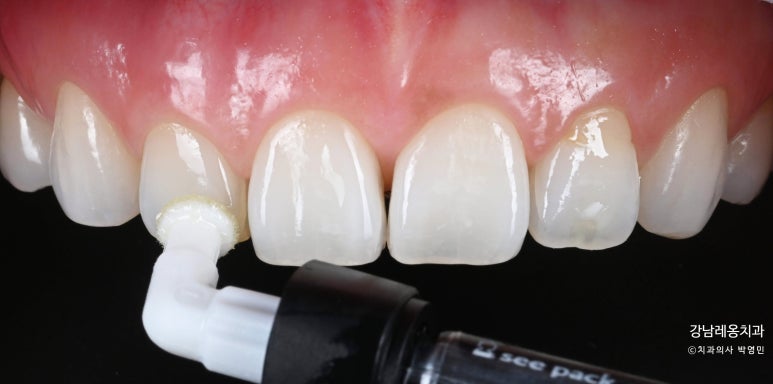

뉴티스 반점치 치료: 아이콘레진

뉴티스 반점치 치료는 아이콘레진을 사용하여

자연치를 최대한 보존하는 방법으로

백색반점을 제거합니다.

미네랄이 소실된 법랑질 표면에

아이콘레진을 여러번 도포하여

탈회된 치아를 메꿔주는 비침습 방식입니다.

3無 아이콘레진

✅ 마취無 ✅ 통증 無

✅ 삭제 無

아이콘레진을 도포하기 전

치아의 백색반점 분포와 정도를 확인하여

치료계획을 세우는 것도 중요합니다.

강남레옹치과는 큐레이(Qray) 정밀분석을 통해

백색반점의 영역과 그 수치를 확인하고

아이콘레진 도포 구역과 레이어링을 결정합니다.